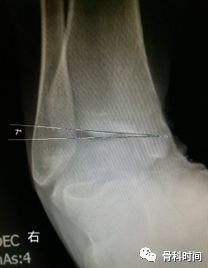

30 岁青年女性,1 年前右踝首次发生崴脚,未行外固定,伤后右踝间断数次崴脚,双侧踝关节应力正位片测量距骨倾斜角,左侧为 0°,右侧 7°,右侧虽尚不能诊断踝关节不稳,但距骨倾斜角增大,对比对侧仍考虑为崴脚后未外固定所致。